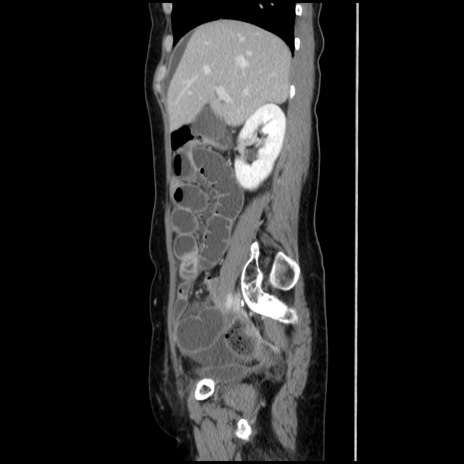

症例32(矢状断像)

【症例】40歳代 女性

【主訴】上腹部痛、嘔気・嘔吐

【現病歴】約9時間前頃から急に上腹部痛、嘔気、嘔吐が出現。改善しないため救急要請。

【既往歴】子宮頚癌(広汎子宮全摘術、放射線療法)、腸閉塞

【身体所見】腹部:平坦、軟、腸雑音亢進、上腹部を中心に腹部全体に圧痛あり。

【データ】WBC 8400、CRP 0.03

冠状断像